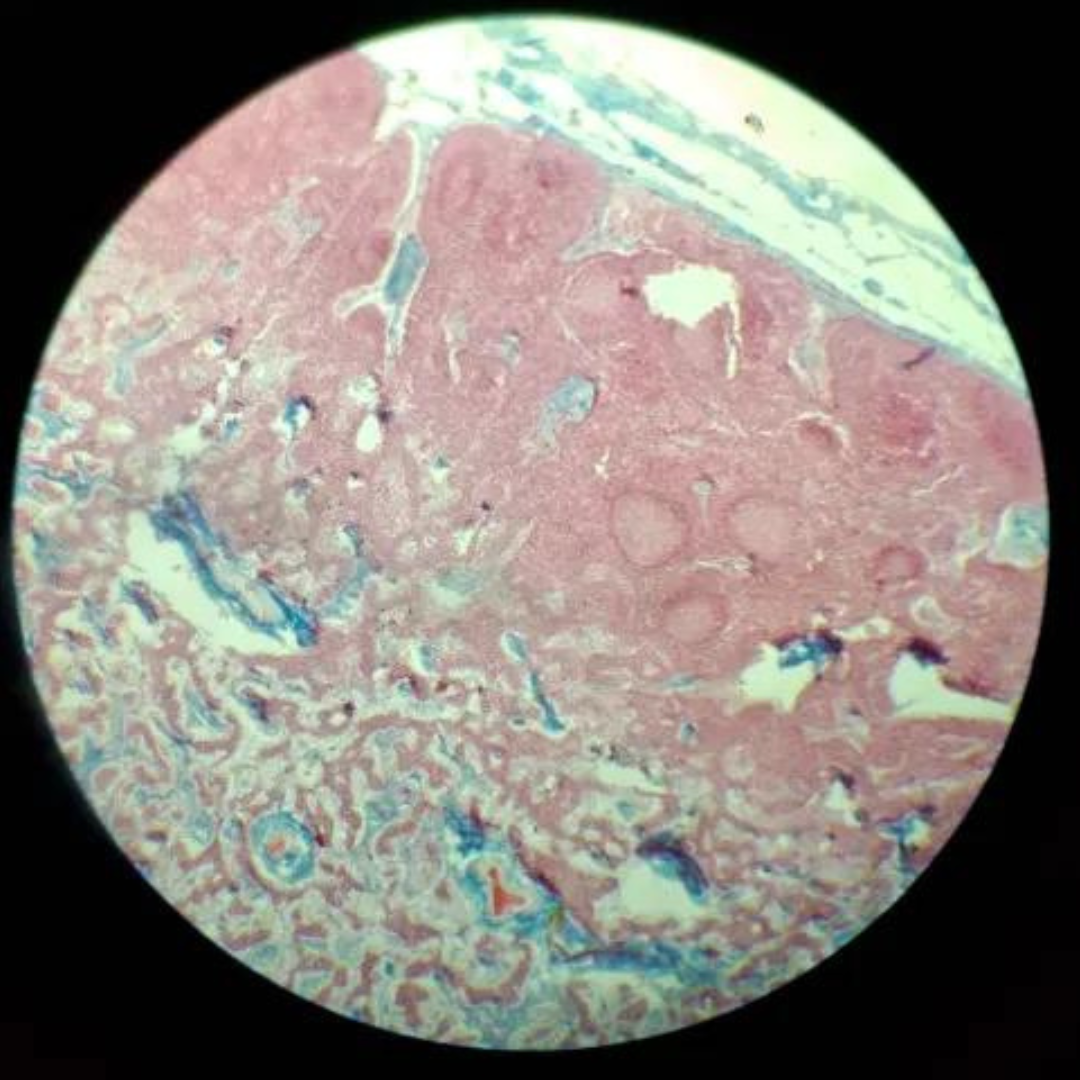

Thymus (Involuted)

30

New cards

Thymus (Involuted)

31

New cards

Thymus (Involuted)